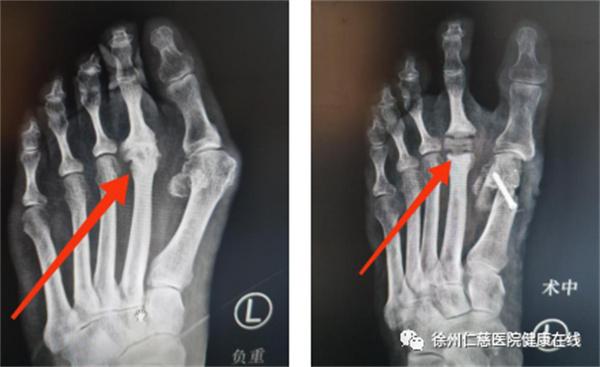

术前术后X光片对比

不仅置换了坏死的跖趾关节,消除疼痛,还矫正了阿姨的拇外翻,并且术后两天就可以下床行走。